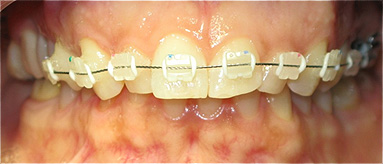

Apinhamento dentário com os dentes caninos em desoclusão (classe II, divisão 2).

![]() |

Após dois anos de tratamento ortodôntico.